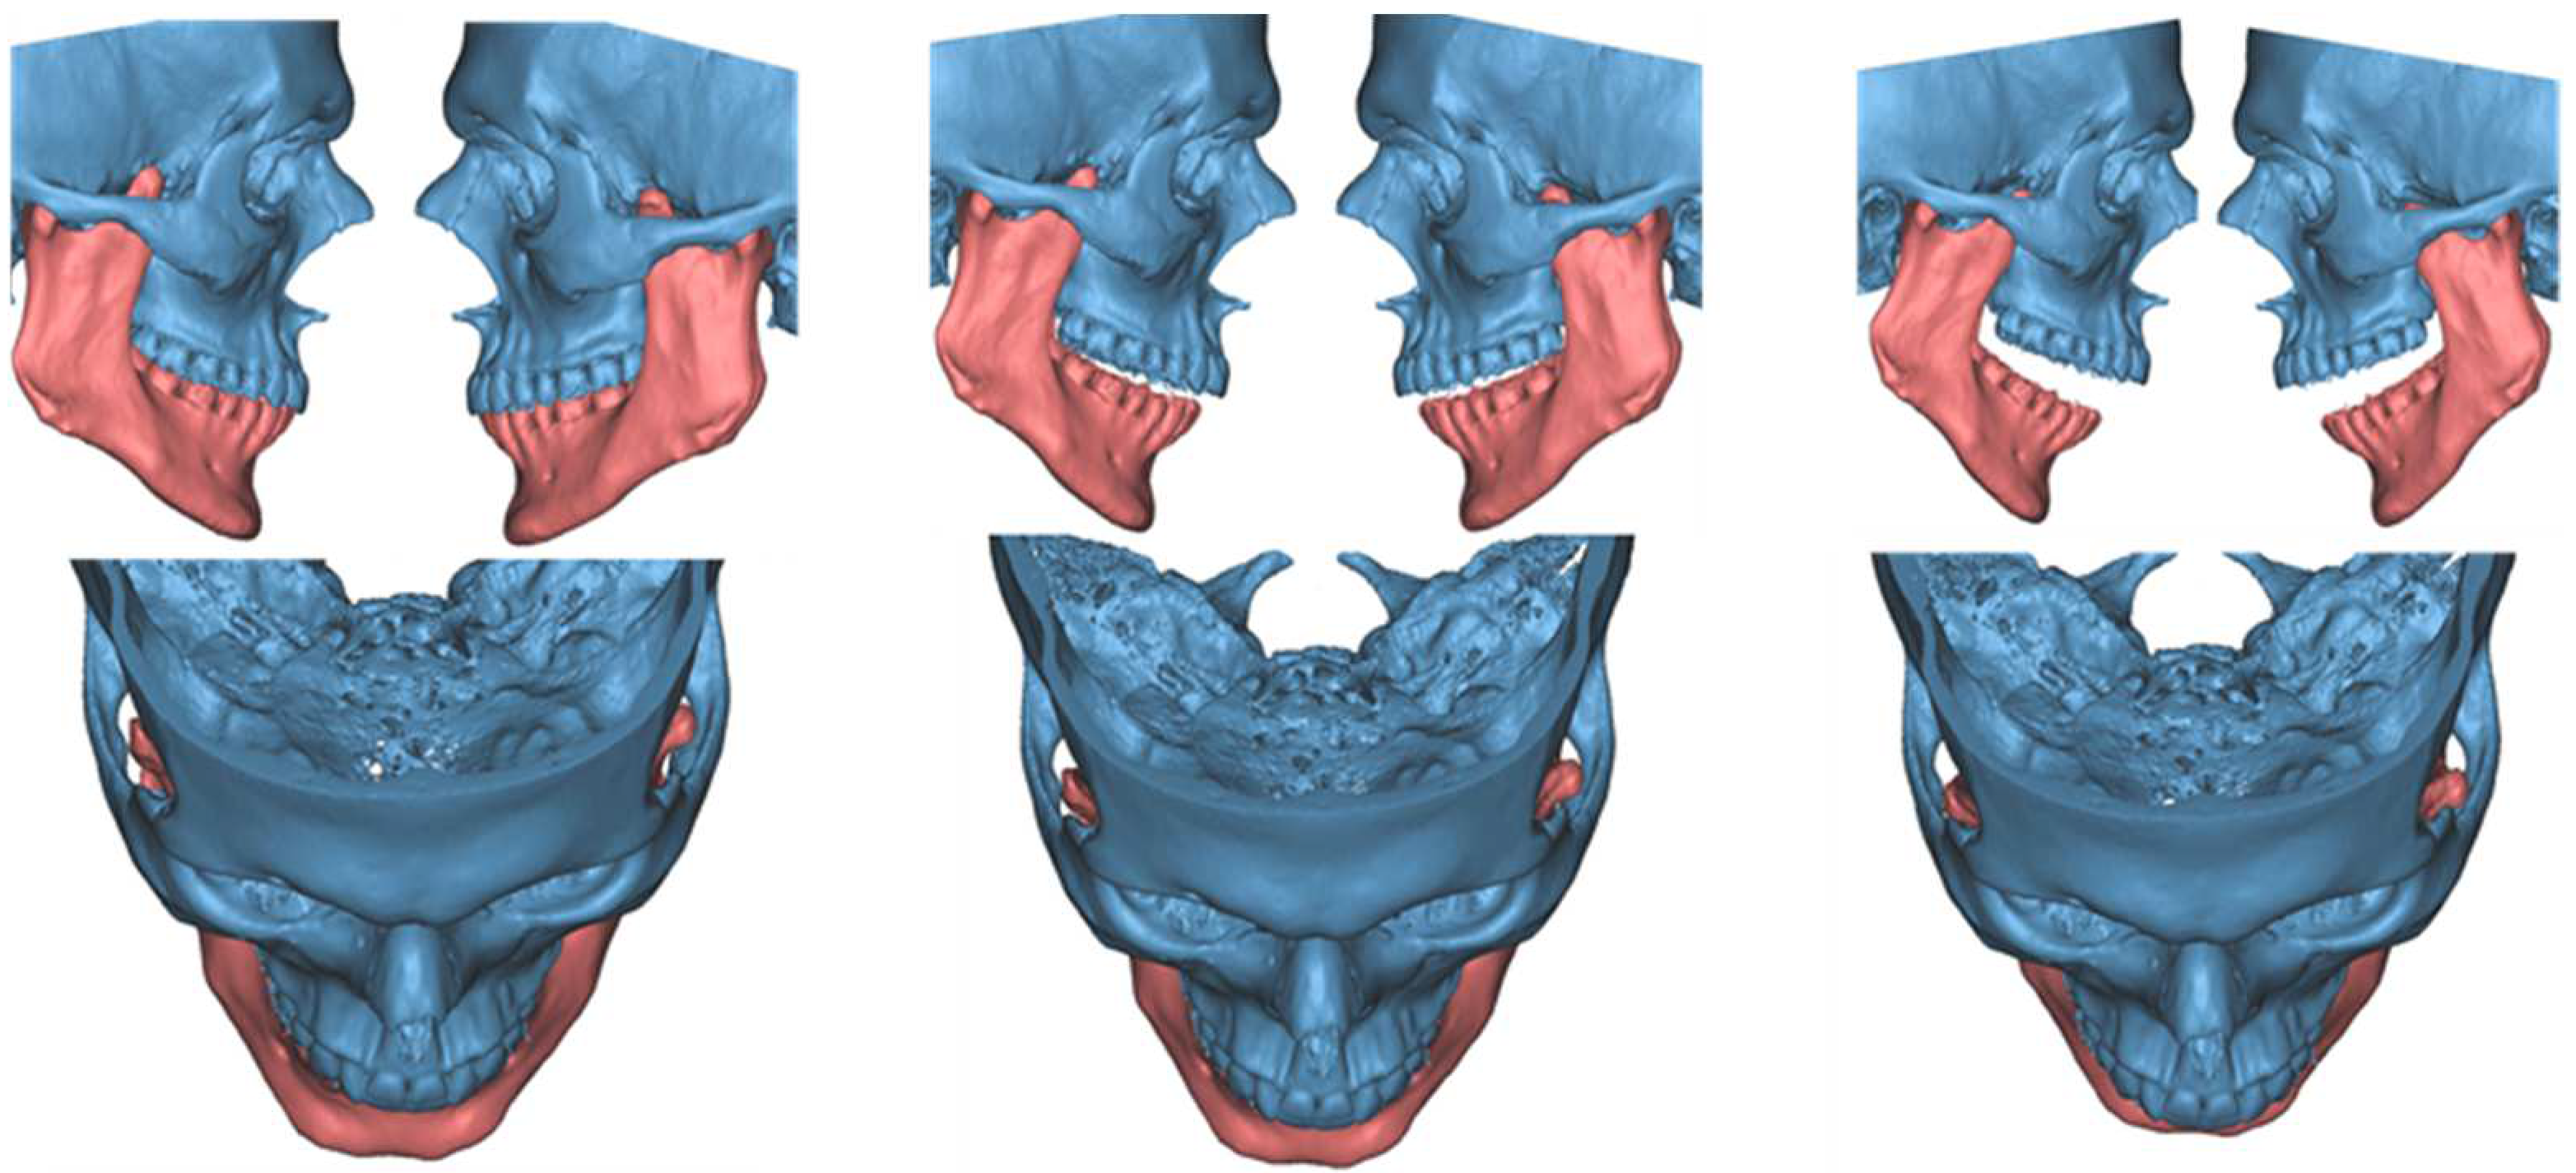

Figure 11.

3-dimensional dynamic reconstruction showing the bilateral pseudojoint determining a bilateral JD.

A 23-year-old male patient presented complaining of a progressive limitation in mouth opening. He did not report any pain. The reduction in the MMO had been worsening over the prior 5 years. There was no history of trauma. Clinical examination revealed an MMO of 20 mm with no deviation (Figure 10). There was no pain during jaw opening. He did not experience pain on palpation of the preauricular area bilaterally. The endfeel was rigid but not painful, and crepitus was perceived at the right TMJ. OPG and TMJ projections showed a lack of translation of the mandibular condyles in the opening and an alteration in the morphology of the CPM bilaterally. MRI was negative for intra-articular causes of ankylosis. CT scans showed a bilateral enlargement of the CPMs with a mushroom-shaped bony outgrowth forming a pseudojoint with the inner aspect of the zygomatic bones, which appeared modeled to the CPMs. This is particularly evident in the 3-dimensional dynamic reconstruction for the virtual surgical planning (VSP) we performed before the surgery (Figure 11). The diagnosis was bilateral CPM hyperplasia, determining a bilateral JD. The patient was scheduled for a bilateral endoscopically assisted intraoral coronoidectomy under general anesthesia with awake fiberoptic intubation. Fibrotic shoots were detected at the pseudojoint between the CPMs and the zygoma. The entire CPM was then removed. At the end of the surgery, the interincisal distance was 50 mm with a mechanical forced opening (Figure 12). The resected specimens showed cortical bone tissue with a regular structure and orientation of the bone lamellae, determining a bilateral JD due to a true CPM hyperplasia. Articular physiotherapy was started one week after surgery using TheraBite jaw motion rehabilitation system TM (Atos medical, Padua, Italy). At 1 month after the surgery, the MMO was 25 mm and increasable after forcing, 2 months later it was 30 mm and 35 mm at 3 months. At 14 months follow-up, the patient MMO was stable at 37 mm, and the radiographic evaluation was negative for recurrence.